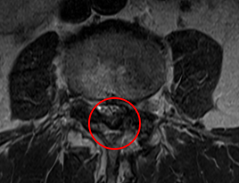

治療前

前回の治療時に発見していたL3/4の脊柱管狭窄症が悪化した可能性があると考え、再度、腰椎MRIで画像検査を実施しました。すると、元々、黄色靭帯が肥厚して狭窄を起こしていたL3/4で、それとは別に椎間板ヘルニアが進行しており、以前よりも狭窄が強くなっていることを確認しました。

なお、前回治療したL4/5はしっかりと減圧されていました。